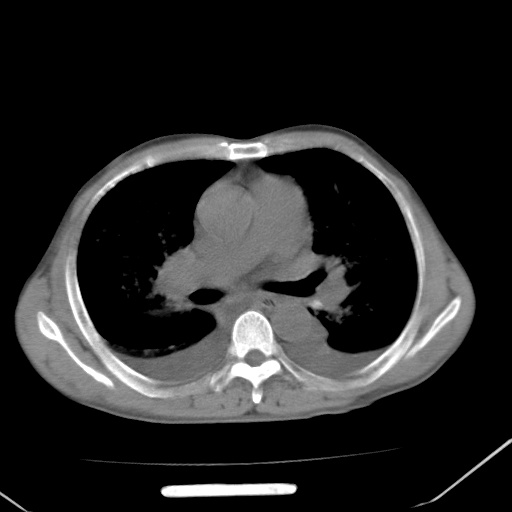

左心房增大,考虑心衰,肺水肿。

心影增大密度略低,双肺磨玻璃样高密度影及双侧胸腔积液,考虑心功能不全继发双肺肺水肿及双侧胸腔积液。心影密度略低,考虑贫血所致。